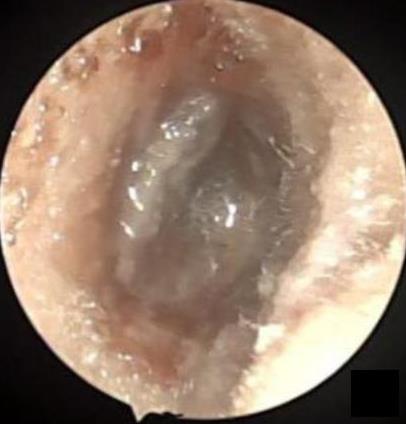

摘要:目的 分析医用生物蛋白胶应用于耳内镜下鼓膜修补术的临床疗效。方法 回顾性分析2022年10月-2023年10月该院收治的60例单纯鼓膜穿孔患者的临床资料,根据手术方法不同,将患者分为研究组和对照组,各30例。研究组术中使用医用生物蛋白胶粘合残余鼓膜和修补材料;对照组术中采用明胶海绵覆盖修补鼓膜。观察两组患者术后的鼓膜愈合情况(鼓膜愈合率、愈合时间、干耳时间和外耳道上下径)和并发症发生情况;于手术前后,采用纯音测听法(500、1 000、2 000、4 000 Hz),测量两组患者气导阈值,观察听力改善程度;采用视觉模拟评分法(VAS)评分,评估患者术后疼痛程度。结果 两组患者术后鼓膜愈合率、愈合时间、外耳道上下径和并发症发生率比较,差异均无统计学意义(P > 0.05)。研究组术后平均气导听阈明显低于对照组,差异有统计学意义(P < 0.05)。研究组术后干耳时间短于对照组,术后第1天疼痛VAS评分明显低于对照组,差异均有统计学意义(P < 0.05)。结论 医用生物蛋白胶应用于耳内镜下鼓膜修补术,可有效地降低气导听阈,缩短干耳时间,减轻患者疼痛,且不增加并发症发生率,值得临床推广应用。